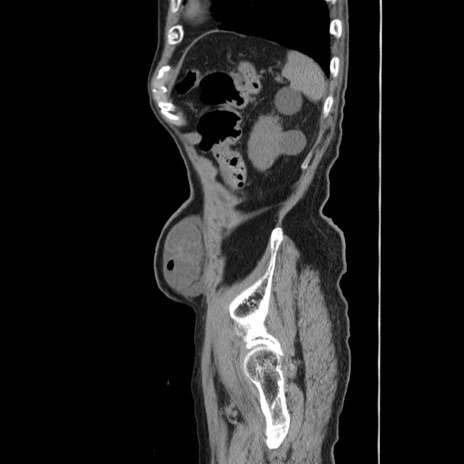

症例24(矢状断像)

【症例】80歳代男性

【主訴】左側腹部痛、嘔吐

【現病歴】本日早朝より左腹部に痛みあり。昼頃嘔吐認めたため、救急要請。

【既往歴】直腸癌(Mile手術)、胆摘

【身体所見】意識清明、BT 35.9℃、BP 221/93mmHg、SpO2 97%(RA) 、腹部:左ストーマ周囲に限局性の腹部膨隆あり。 膨隆部自発痛・圧痛あり・軟。

【データ】WBC 7700、CRP 0.09